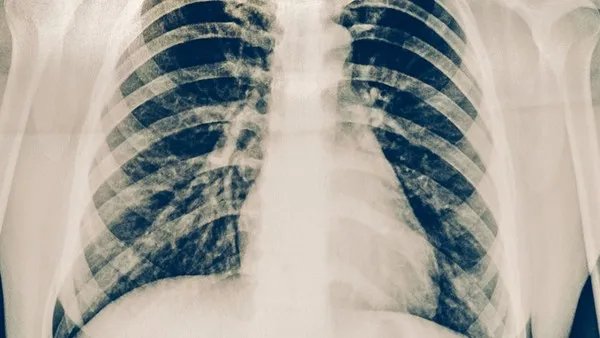

肺癌是常见的呼吸系统恶性肿瘤,病因主要与吸烟、大气污染、电离辐射和营养状况密切相关。肺癌的常见症状反复刺激性咳嗽、痰中带血、不明原因咯血、胸痛、胸闷气短等。伴随着大量胸水,呼吸困难的情况也有可能发生。肺癌患者能活多久,关键取决于确诊时肺癌类型和疾病的临床分割。